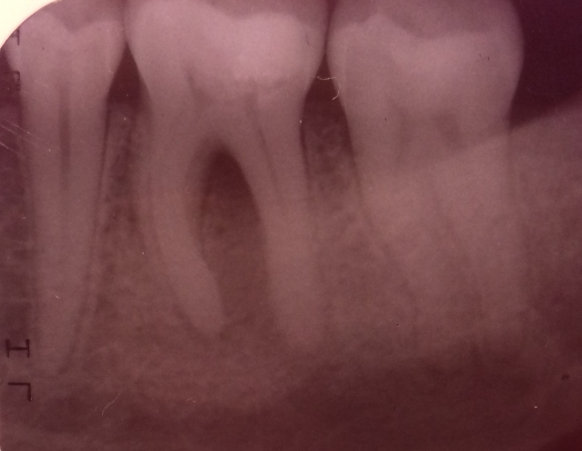

Здравствуйте. При принятии твердой и сладкой пищи, а также при ежедневной чистке зубов возникает ноющая боль в зубе (крайний левый на нижней челюсти). Стоматолог сказал, что есть небольшой кариес, поставили пломбу. Прошло уже три дня, а зуб всё равно ноет при накусывании. От чего это может быть и что делать в данной ситуации?

Добрый день . Скорее всего ваш стоматолог поставил неправильный диагноз или пломба завышает . Рекомендую обратиться на очный прием и после снимка вам все подробно расскажут. Не тяните , потеря времени может привести к потере зуба.